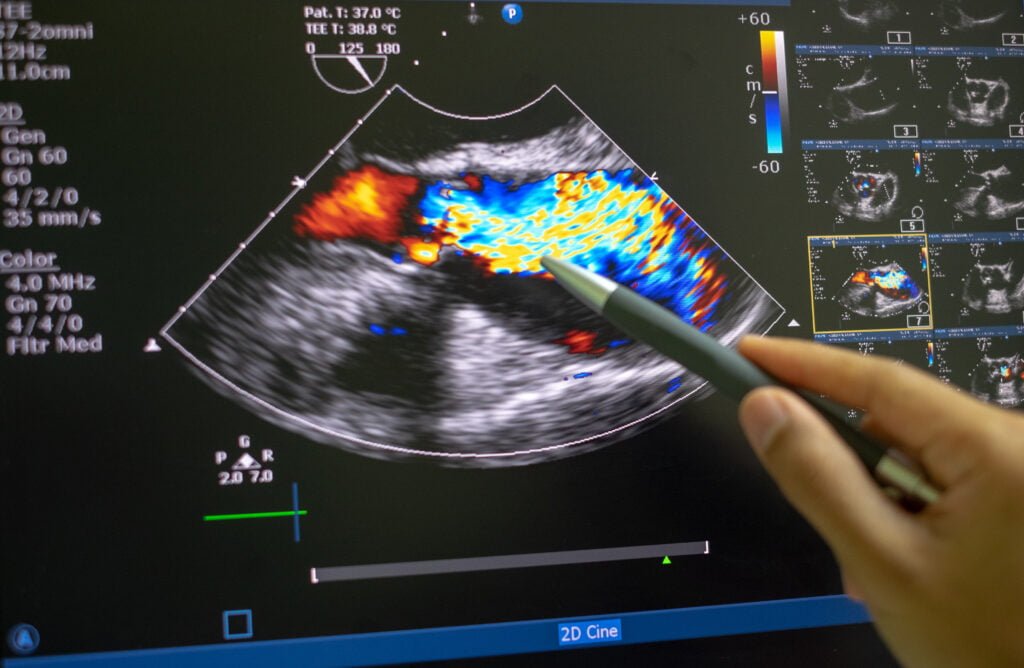

Oexame deecocardiograma, ou também chamado de ecodopplercardiograma, é uma ultrassonografia exame de imagens gerado pela emissão e captação de ondas de ultrassom do coração.ODoppleré uma técnica associada à ultrassonografia, que permite a avaliação do fluxo sanguíneo pelas válvulas cardíacas.

EcocardiogramacomDoppler: utilizado para observar comoosangue flui através das câmaras do coração, válvulas cardíacas e vasos sanguíneos. A circulação do sangue reflete ondas de som paraoaparelho.

mediclinic@.-EcocardiogramacomDoppler– permite avaliarosfluxos de sangue (velocidade e direção) dentro do coração e nas grandes artérias,oque acrescenta importantes informações sobreoseu funcionamento.

Assim, a ecocardiografiacomanáliseDopplerpode ser considerada um método moderno e extremamente informativoparaodiagnóstico de patologias cardíacas. Ele permite queosmédicos verifiquem a estrutura do coração, acompanhem seu trabalho, bem comoomovimento do fluxo sanguíneo, sua turbulência e velocidade.

Oecocardiogramabidimensionalcomdoppleré um exame de imagem, que usa tecnologia avançada para avaliar a saúde do coração, sua anatomia, fluxo sanguíneo na região e a função cardíaca como um todo.